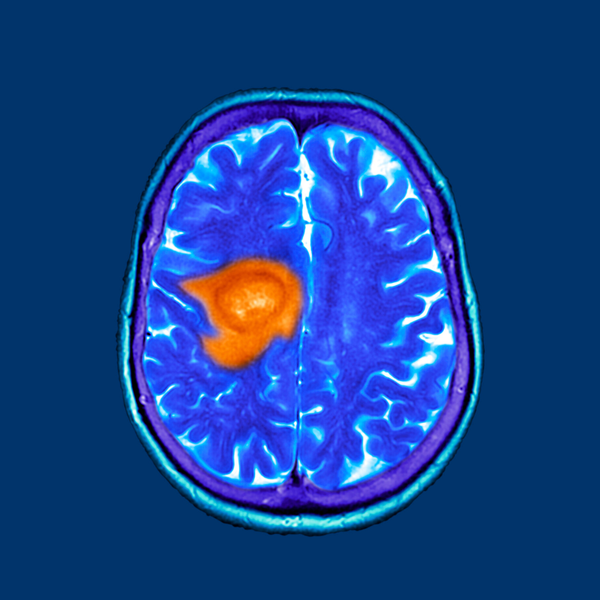

O glioblastoma, também conhecido como glioblastoma multiforme, é um tipo de câncer cerebral altamente agressivo e incurável. Neste artigo, exploraremos diversos aspectos dessa doença devastadora, incluindo sua nomenclatura, epidemiologia, diagnóstico, tratamento, cirurgia máxima segura e opções complementares de tratamento, levando em consideração a situação clínica do paciente. Nomenclatura e Epidemiologia

O conhecido senador dos Estados Unidos John MacCaine, considerado herói da Guerra do Vietnã, é mais uma vítima do Glioblastoma. O Glioblastoma ou GBM é o tumor maligno do cérebro mais comum nos adultos. De uma classificação de 1 (I) a 4 (IV), o Glioblastoma é classificado como IV, ou

Os tumores cerebrais são graduados de 1 a 4 com base nas anormalidades de suas células visto ao microscópio (necrose, proliferação celular etc). O grau 1 é o menos maligno, possuindo menos anormalidades, enquanto o grau 4 é o mais maligno, apresentando mais anormalidades. Um mesmo tumor pode conter células